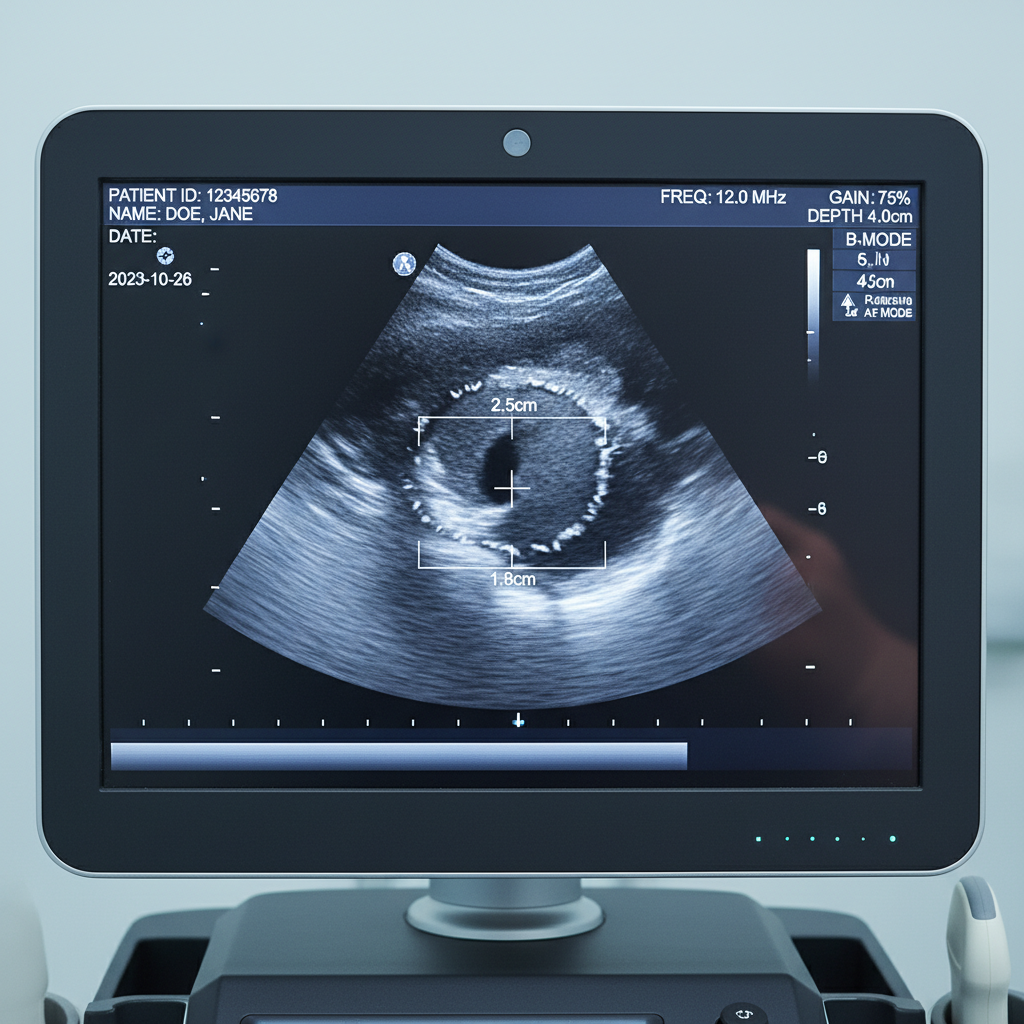

- 영상 검사: 초음파는 멍울의 성격을 파악하는 데 가장 기본적이고 유용한 검사예요. 필요시 유방 촬영술(맘모그램), MRI, CT 등을 추가로 진행할 수도 있습니다.